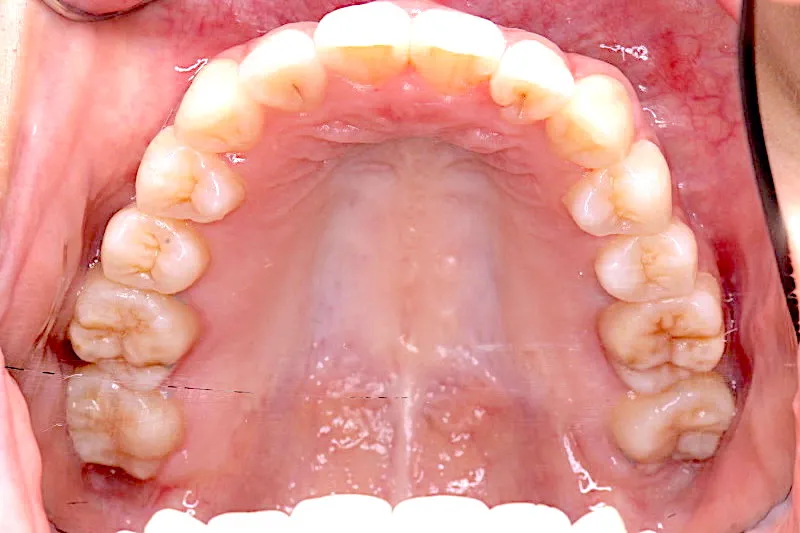

治療終了後

治療前と治療後で下の歯の銀歯がなくなっています。

これは銀歯の第1大臼歯を抜いて第2大臼歯、第3大臼歯の親知らずを使いました。

コルチコトミーという矯正法で歯根への負担を軽減しながら治療しました。